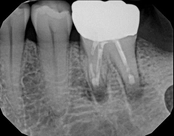

Non-surgical root canal treatment:

Before

Immediately After

6-month follow-upThis patient presented with pain when chewing. Diagnostic testing was done and determined it was the lower molar. The diagnosis was: pulpal necrosis, symptomatic periradicular periodontitis. Root canal treatment was performed with laser disinfection. The tooth had a crown and we accessed the tooth through the crown. We saved the tooth and the crown.